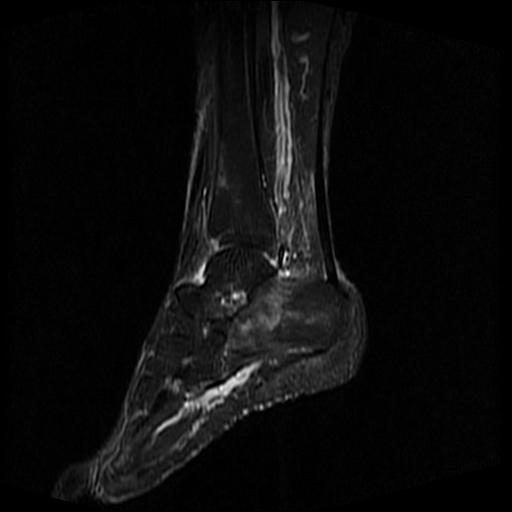

女性,70岁,右侧跟骨疼痛2个月,负重时加剧,不负重时不疼。

胫骨下段,跟骨、距骨可见斑片状异常信号区;考虑:转移瘤

跟骨病灶呈片状,边界模糊,可否考虑隐匿性骨折呢?

跟骨长t1长t2信号异常,边缘模糊(肿瘤一般边界清楚,故肿瘤不考虑),压脂像呈高信号--骨髓水肿(炎症?)。